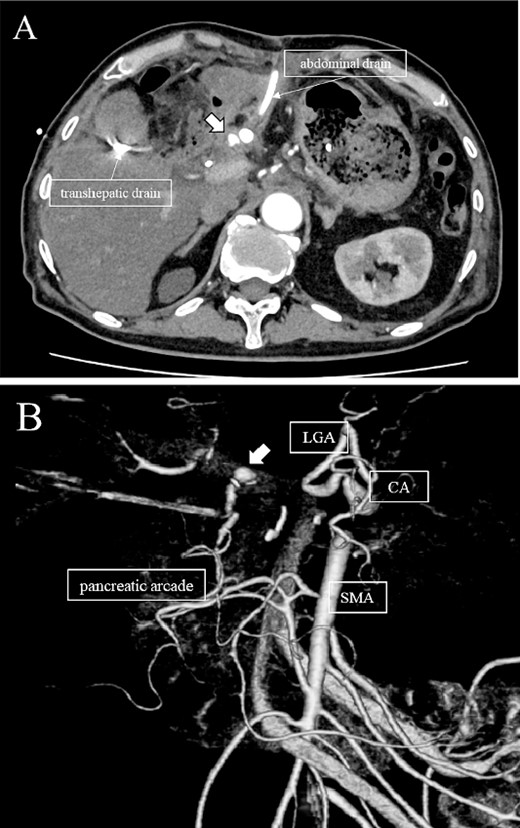

A 76-year-old man underwent DP-CAR after eight courses of gemcitabine and nab-paclitaxel therapy as preoperative chemotherapy for pancreatic body cancer with celiac artery invasion (Fig. 1). As the celiac axis had not invaded into the bifurcation of the left gastric artery, a modified DP-CAR (left gastric-preserving) was performed. Although post operative pancreatic fistula (POPF) developed on postoperative Day (POD) 5, and biliary fistula developed on POD 17. Bile leak was thought to be caused by the rupture of the choledochal duct due to bile duct ischemia caused by CHA transection. Subsequently, both the POPF and biliary fistulae were drained and fistulated. However, on POD 47, the drainage fluid became bloody. Contrast-enhanced computed tomography (CeCT) revealed a pseudoaneurysm at the junction of the gastroduodenal artery (GDA) and proper hepatic artery (PHA) (Fig. 2A and B).

(A, B) CT on postoperative day 48. Contrast-enhanced CT showing a pseudoaneurysm at junction of the GDA and PHA (arrow).